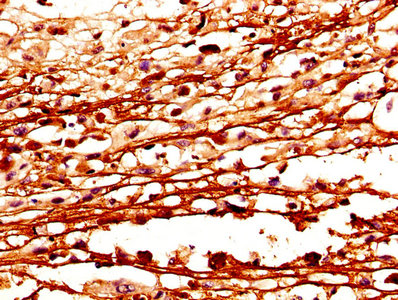

IHC image of CSB-PA006099DA01HU diluted at 1:400 and staining in paraffin-embedded human melanoma performed on a Leica BondTM system. After dewaxing and hydration, antigen retrieval was mediated by high pressure in a citrate buffer (pH 6.0). Section was blocked with 10% normal goat serum 30min at RT. Then primary antibody (1% BSA) was incubated at 4°C overnight. The primary is detected by a biotinylated secondary antibody and visualized using an HRP conjugated SP system.